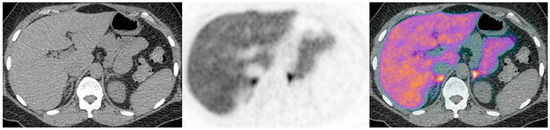

Figure 3. Illustrative case 3: A 42-year-old woman had been diagnosed with hypertension and hypokalaemia 15 years previously in pregnancy. She rotated through trials of various anti-hypertensive medications before achieving reasonable control with spironolactone, together with additional potassium supplementation. A biochemical diagnosis of primary aldosteronism was made following a failure to suppress aldosterone on a saline infusion test. CT findings were equivocal, but with a suggestion of possible subcentimetre nodules bilaterally on CT (a). There were no discrete ‘hot nodules’, with symmetrical bilateral uptake on 11C-metomidate PET-CT (b,c). Her bilateral disease is currently managed medically.